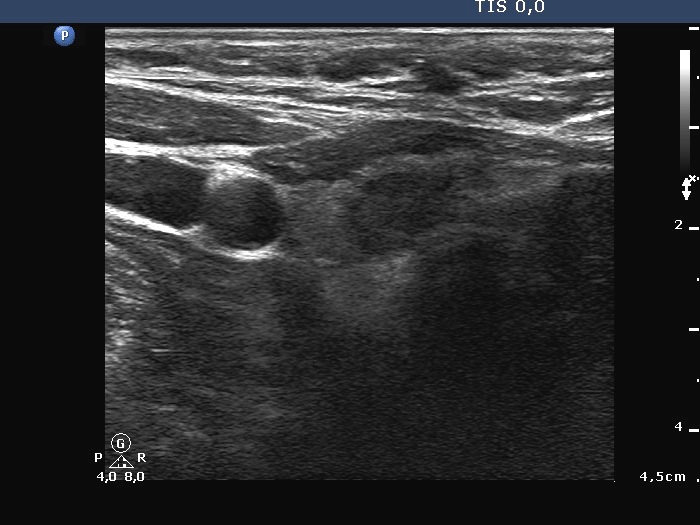

Follicular carcinoma - Case 1. |

Ultrasonography: there was a small hypoechogenic nodule in the right, while a large one in the left lobe. The left nodule was deeply hypoechogenic, had irregular, blurred borders. This lesion did not exhibit perinodular or intranodular blood flow.